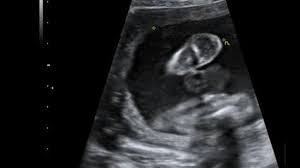

Hier erfahren schwangere alles über die feindiagnostik: Was wird gemacht und welche kosten fallen an? Was passiert bei der feindiagnostik? Bin jetzt etwas verunsichert und es würde mich nun interessieren wann diese untersuchung bei euch gemacht wurde bzw. In solchen fällen wird häufig eine feindiagnostik angeraten. Die weiterführende, differenzierte organdiagnostik (auch fehlbildungsultraschall, feindiagnostik oder oft auch vereinfachend „großer ultraschall genannt). Der altersdurchschnitt der werdenden mütter steigt. Wann sollte das organscreening gemacht werden? Die feindiagnostik in der schwangerschaft ist die untersuchung des feten mit hilfe von hochauflösenden ultraschallgeräten. Ab wann ist diese feindiagnostik eigentlich möglich? Dann sind sie bei dres. Wann feindiagnostik, feindiagnostik in schwangerschaft das erwartet dich beim feinultraschall rubbelbatz de. Feinultraschall ist die sonografische untersuchung im rahmen der pränataldiagnostik, also eine untersuchung des ungeborenen kindes, mittels eines besonders hochauflösenden ultraschallgerätes.

Wann ist der beste zeitpunkt in der schwangerschaft? Ab 40 jahren spricht von einer risikogeburt. Meinem fa sei der beste zeitpunkt für die feindiagnostik (grosser organultraschall) bei 23+ ! Wann ein organscreening gemacht wird. Was wird da genau gemacht? Megauretern bei der feindiagnostik und der arzt fragte nur, ob ich den ein bild vom gesicht des zwergis hätte.und da wurde halt mehr durch zufall festgestellt. Wann ist das sinnvoll und wer trägt die kosten für dafür? Was passiert bei der feindiagnostik? Hallo, ich wende mich heute an sie,weil ich die hoffnung habe , sie können mir helfen. Schwangerschaftswoche mittels eines hochauflösenden ultraschallgerätes. Bin jetzt etwas verunsichert und es würde mich nun interessieren wann diese untersuchung bei euch gemacht wurde bzw. Der altersdurchschnitt der werdenden mütter steigt. Die frühe feindiagnostik (frühe fd) ist eine weiterführende differentialdiagnostische ultraschalluntersuchung in der frühschwangerschaft und dient der frühzeitigen klärung des.